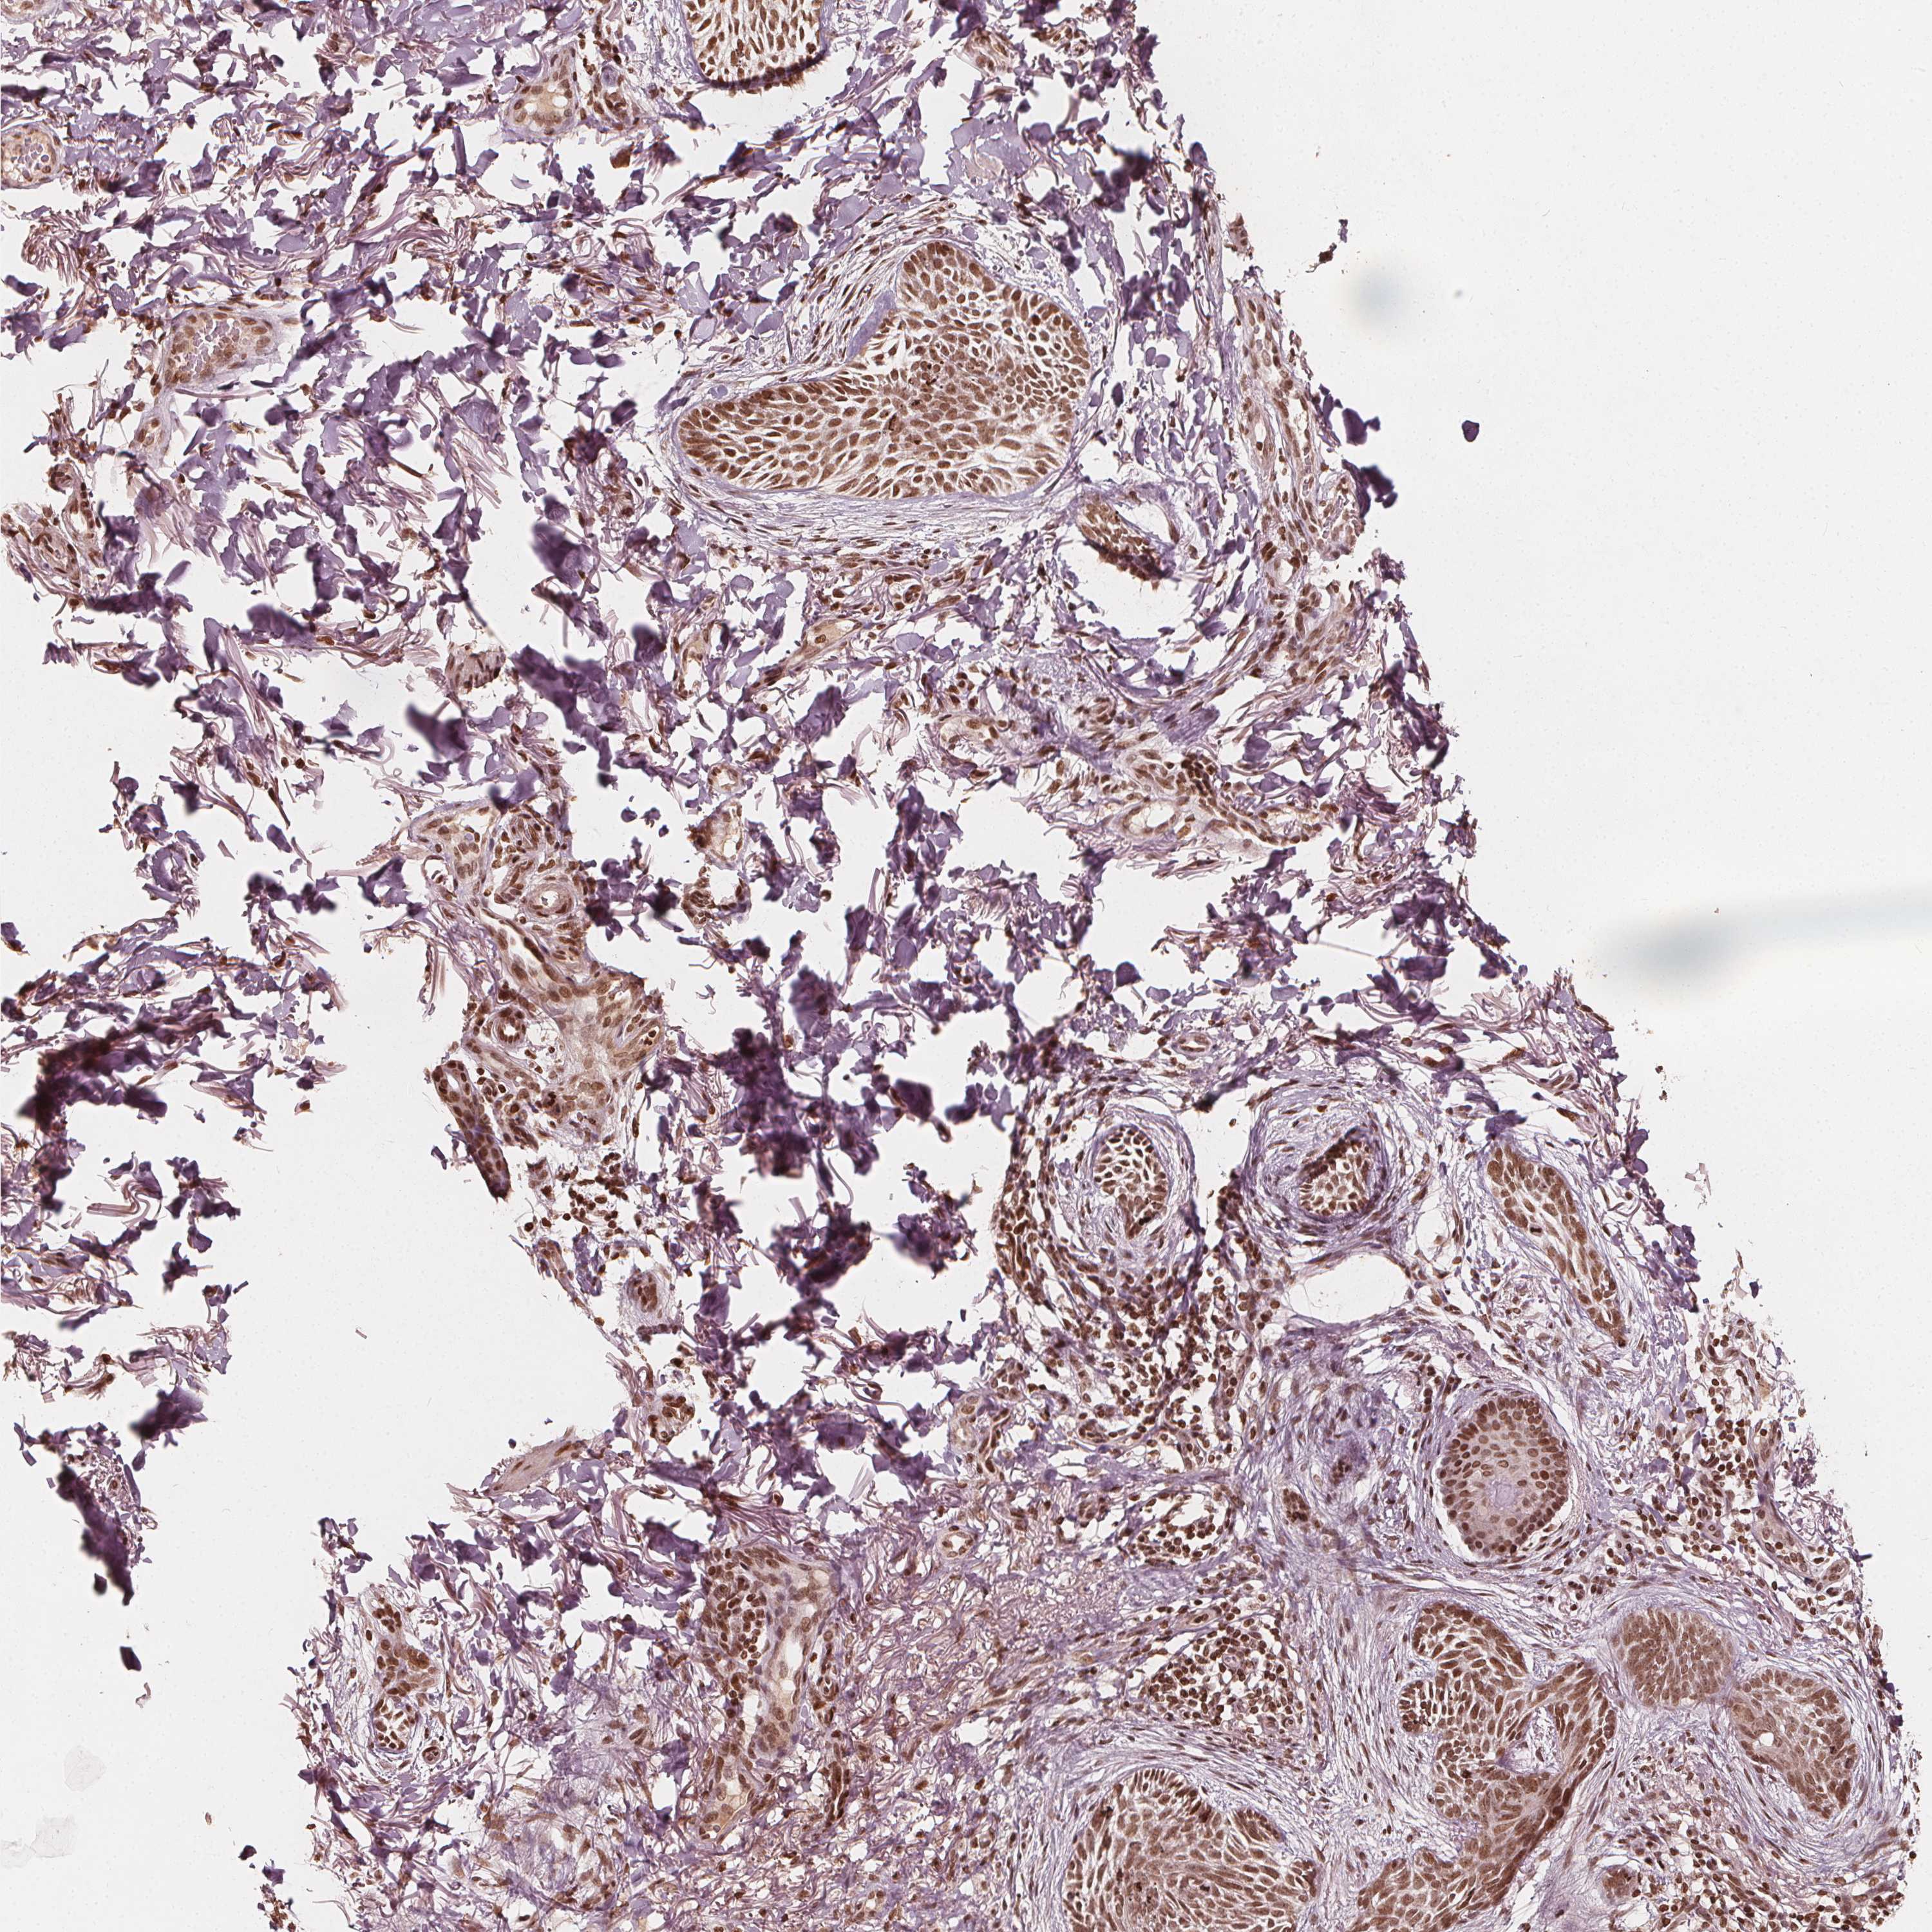

SKIN CANCER - Protein expressioni

A mouse-over function shows sample information and annotation data. Click on an image to view it in a full screen mode. Samples can be filtered based on level of antibody staining by selecting one or several of the following categories: high, medium, low and not detected. The assay and annotation is described here.

Each image is clickable and will lead to virtual microscopy that enables deeper exploration of all samples and also displays staining intensity scores, fraction scores and subcellular localization as well as patient and tissue information for each sample.

Antibody CAB069990

Squamous cell carcinoma, metastatic, NOS

Squamous cell carcinoma, NOS